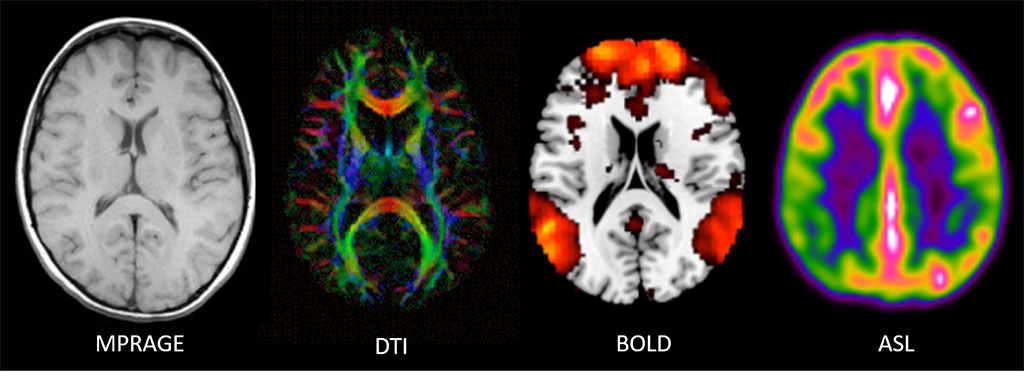

Structural MRI consists of scan sequences that provide images of the brains structure, allowing examination of the anatomy and pathology of the brain. These images can be used for clinical diagnostics as well as for research purposes. A few of the most common scans are detailed below (Fig. 3).

Magnetization Prepared - Rapid Gradient Echo (MPRAGE) – 3D high resolution T1 structural scan used to measure tissue volumes (WM, GM, CSF) whether whole brain or by region. This scan can also provide information to derive cortical thickness. Specifically, the human cerebral cortex is a highly folded sheet of neurons and structural scans such as these capture this information. T1 structural scans also routinely provide spatial information for functional scans since those tend to have lower resolution. More recently, they have also been used to guide TMS mapping and therapy.

Diffusion Tensor Imaging (DTI) – DTI measures the diffusion process of water along white matter tracts via a series of pulse sequences being performed in multiple directions. DTI provides details about axonal architecture and direction, which provide measures of axonal integrity (fractional anisotropy [FA]) and axonal pathways or tracts (tractography).

Figure 3. Far left: Magnetic resonance images for a T1-weighted structural scan; Center left: a diffusion tensor imaging (DTI) scan showing tractography; (colors reflect different directions of axonal tracts); Center right: brain activity from a resting blood-oxygen-level dependent (BOLD) scan overlaid on a structural scan; Far right: and a cerebral blood perfusion image derived from an arterial spin labeling (ASL) scan.

Blood-oxygen-level-dependent (BOLD) fMRI - BOLD measures brain activity by detecting associated changes in blood flow. Specifically, BOLD relies on detecting properties of oxygenated and deoxygenated hemoglobin in the blood to see images of changing blood flow in the brain associated with neural activity. Neurons do not store their own fuel sources (e.g., oxygen), so when neurons activate, they pull what they need out of the blood, including oxygen. The change from oxygenated to deoxygenated blood in a given area is a proxy of brain activity MRI can detect. Neural activity can be measured using BOLD during a resting-state, not performing an explicit task, or an active state, when performing an explicit task, such as a cognitive challenge (e.g., working or episodic memory, reward, emotion, social cognition). BOLD provides measures of what regions are active when, and/or what functionally connected regions are active together.